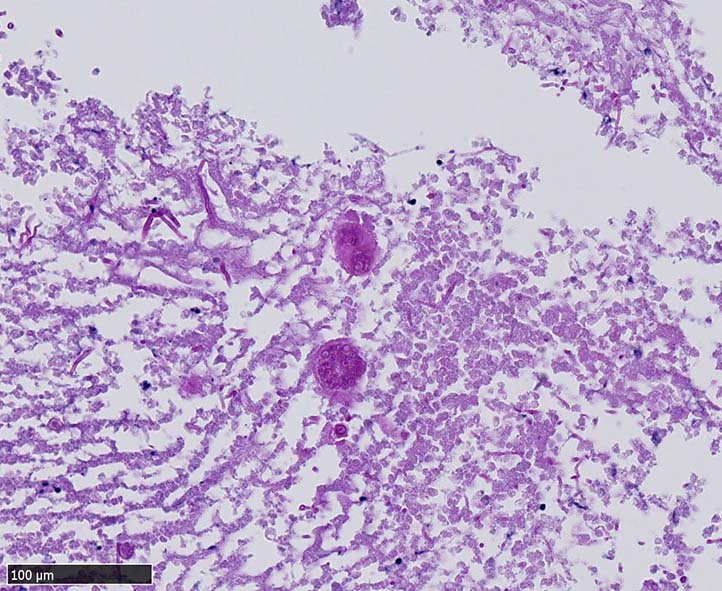

空洞辺縁には5~50μm径ほどの球状体(spherule)が形成され, 大型の球状体の一部は内部に2~10μm径ほどの内生胞子(endospore)を容れている. 内生胞子はPAS, Grocottで染色される.

本症例では空洞壁部分に球状体のほか多数の菌糸発育が観察された.

栄養型(菌糸および分節型分生子)と寄生型(内生胞子を多数容れた球状体)*1